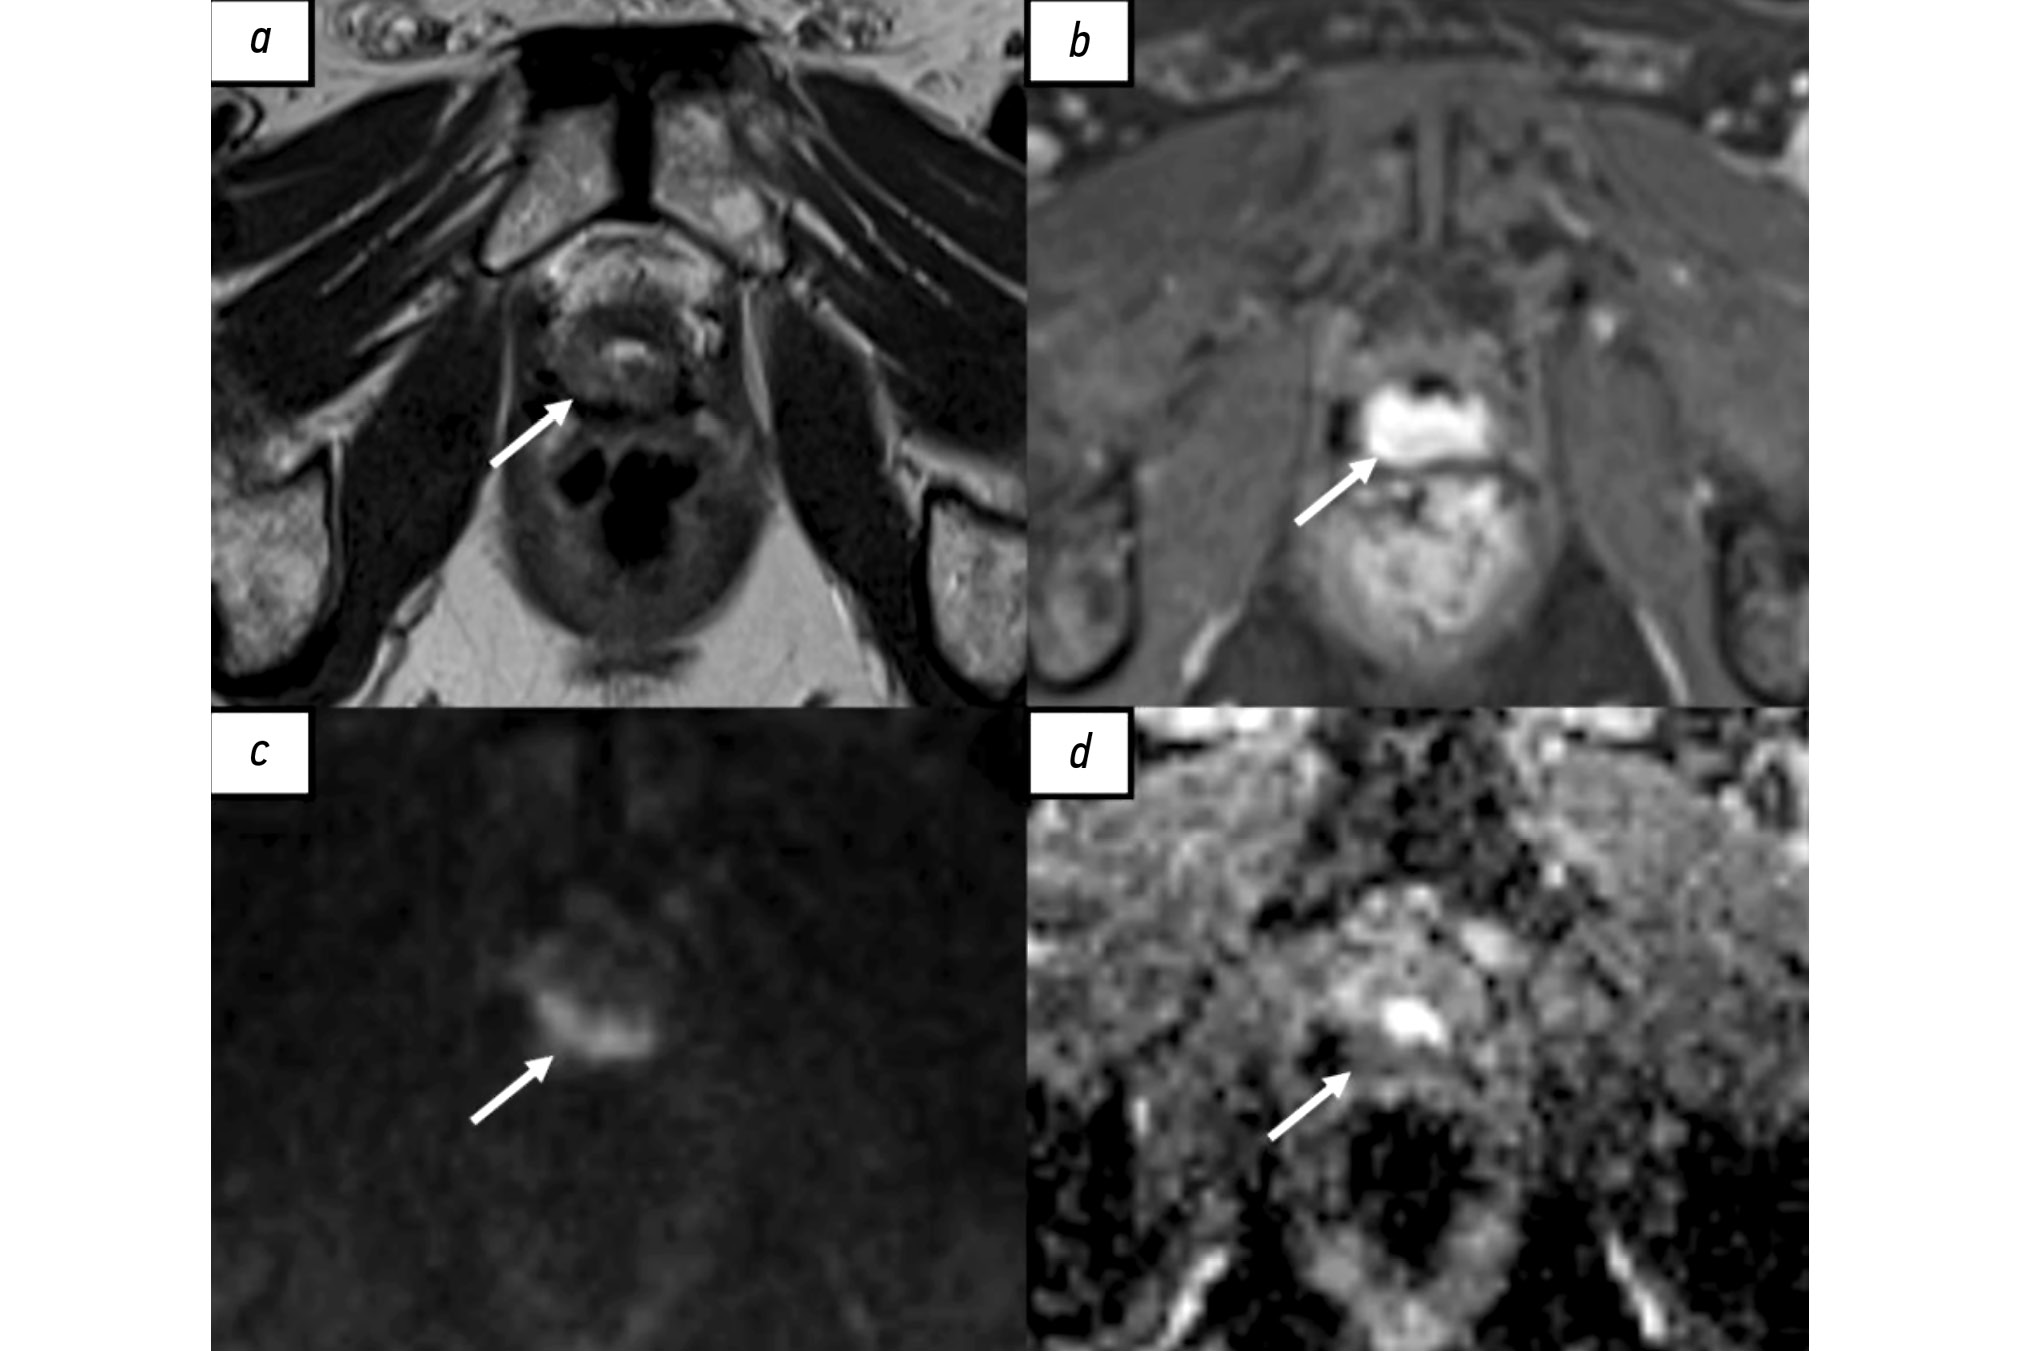

Hypophysitis is a rare inflammatory disorder that affects the pituitary gland and infundibulum, stems from autoimmune, infiltrative, infectious, or unknown causes. Its clinical diagnosis can be challenging because several pituitary lesions, including adenomas and metastases, may clinically present with similar characteristics. Magnetic resonance imaging is crucial for diagnosing suspected cases of hypophysitis and categorizing them as adenohypophysitis (anterior pituitary gland involvement) or infundibulo-neurohypophysitis (pituitary stalk and posterior pituitary involvement). Hypophysitis can be categorized as primary (autoimmune) or secondary due to local lesions (e.g., granulomas, cysts, adenomas) or systemic diseases (e.g., sarcoidosis, Wegener’s granulomatosis). Different factors may have impact on clinical course of hypophysitis. Among them background treatment. These cases have not been sufficiently studied and are practically not presented in publications.

A 37-year-old female with a history of hyperprolactinemia was being treated symptomatically with cabergoline. At first magnetic resonance imaging heterogeneity of the hypophysis was revealed. In September 2021 the follow-up magnetic resonance imaging revealed an increase in the size and heterogeneity of the pituitary gland. In December 2021, the patient developed severe COVID-19-associated pneumonia and was treated with corticosteroids and oxygen support. In May 2022 magnetic resonance imaging revealed a marked increase in the size and heterogeneity of the pituitary gland. Significant clinical and radiological improvement were stated after adding prednisone (10 mg in the morning and 5 mg in the evening) to her treatment.

The patient was followed-up during the COVID-19 pandemic. The management and imaging studies of such patients may be tricky due to the effects related to COVID-19 and its treatment.

During monitoring of hypophysitis, physicians should consider the impact of COVID-19 treatment, particularly corticosteroid therapy, when evaluating the radiological changes.